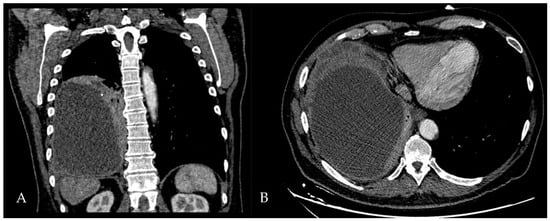

A 60-year-old Caucasian man was admitted to our hospital with a history of worsening pain at the base of the right hemithorax and feeling generally unwell for over one month. The patient’s past medical history included coronary heart disease, with a percutaneous coronary intervention in 2014. He smoked a half-pack of cigarettes per day for 40 years and had no history of respiratory disease. The CT chest scan showed a fluid collection in the medium–lower parts of the right hemithorax with thickened walls and contrast enhancement (Figure 5). This collection appeared in continuity with further smaller fluid collections with thickened walls, contrast enhancement, and confluence and caused the complete atelectasis of the middle and lower lobes and the partial atelectasis of the upper lobe, as well as middle and inferior lobar bronchus occlusion.

A 61-year-old female patient with obesity, discoid lupus, bipolar disorder, arterial hypertension, and hypothyroidism was admitted to our Respiratory Unit for respiratory failure and evidence of a large complex PEff on her chest CT, which also revealed complete atelectasis of the right lower lobe (RLL) and almost-complete atelectasis of the middle lobe (ML) and right upper lobe (RUL) (Figure 6). There was also a solid tissue surrounding the right main bronchus and its main branches, which was suspected to be neoplastic. It had a central hypodense area consistent with necrosis.

Peripheral enhancement of the pleural layers was also observed.

Figure 5. Chest CT scan of the mediastinal window in the coronal (A) and axial (B) plane, showing fluid collection in the medium–lower parts of the right hemithorax (maximum axial dimeters of 19 × 13 cm; craniocaudal extension of 16 cm) with thickened walls and contrast enhancement. There is also a complete atelectasis of middle and lower lobes and partial atelectasis of the upper lobe.

Figure 6. Chest CT scan of the mediastinal window in the coronal (A) and axial (B) plane, showing a large right pleural effusion, occupying almost the entire hemithorax with organized appearance. There is also a complete right lower lobe atelectasis and almost-complete right middle and upper lobe atelectasis with sparing of anterior sectors.